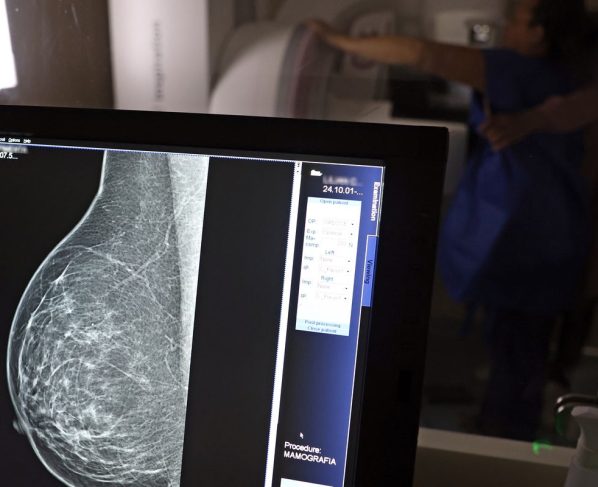

No Outubro Rosa, o Instituto Nacional de Câncer (Inca) estimou 73.610 novos casos este ano no país. É o câncer que mais mata mulheres no Brasil. As mulheres em tratamento pela doença têm o direito de receber o auxílio-doença ou o benefício de prestação continuada.

A vice-presidente da Comissão de Previdência Social Pública da Ordem dos Advogados do Brasil do Rio de Janeiro (OAB-RJ), Danielle Guimarães, destaca que o câncer de mama é uma das doenças que mais afetam mulheres no Brasil, impactando não apenas a saúde física e emocional, mas também a capacidade de trabalho e a segurança financeira das pacientes.